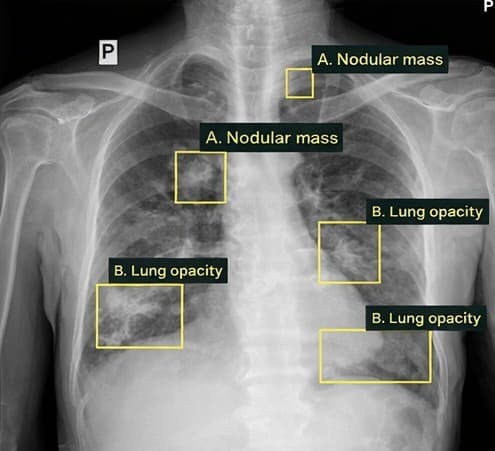

Lung tumor

Tuberculosis

TB | 0.94Sputum collection pending

Tuberculosis | 0.94Sputum collection pending